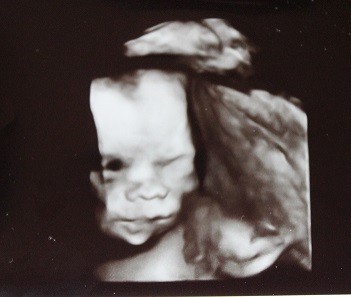

młody klocek, fika elegancko, mam śmieszne zdjęcie jak mruga do nas jednym oczkiem haahhaha w prezencie dostałam film z wizyty, więc dziś przegrałam a jutro mojej babci wyślę